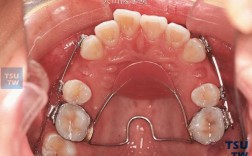

平导,全称是平面导板,是牙齿矫正(正畸)治疗中一种常用的功能性矫治器或辅助装置,它通常由树脂材料制成,戴在上颌牙齿(上牙弓)上,覆盖在前牙区域(主要是切牙和尖牙),而后牙区域(磨牙)是不接触的。

平导的核心作用是打开咬合,特别是解决深覆合问题,它的原理基于肌肉的力量和牙齿的移动:

- 当患者戴上平导后,上下后牙无法接触(被导板隔开)。

- 为了咀嚼、说话或吞咽,患者必须用下前牙咬在平导的平面上。

- 这个持续的下前牙对平导的咬合压力,会传递给上前牙,产生一个压低的力量,促使上前牙向牙槽骨内移动(压入)。